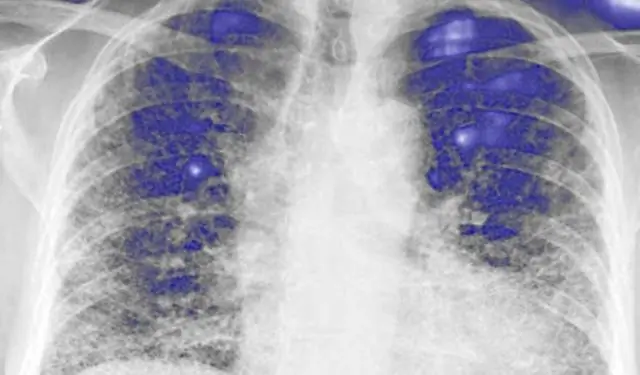

В 2000 году отобранная группа международных экспертов в области интерстициальных заболеваний легких представила руководство по диагностике и лечению IPF (5). Из-за недостатка имеющихся данных и относительно незрелой области методологии руководства этот документ был разработан с использованием общепринятого консенсусного подхода, основанного на мнениях нескольких членов экспертной группы, без систематического обзора литературы или формального качества оценки доказательств. Несмотря на это, этот документ, который в то время считался современным для этой болезни, предоставил полезное руководство для врачей в диагностике и ведении пациентов с IPF. В течение следующего десятилетия все больше исследований в области IPF были опубликованы на основе этого руководящего документа. По мере накопления доказательств практикующим врачам стало обременительно тщательно анализировать и интерпретировать самые последние исследования. Чтобы решить эту проблему и улучшить предыдущий документ, в руководящем документе 2011 года использовался основанный на фактических данных подход, а именно подход GRADE (оценка, разработка и оценка классификации) для разработки руководящих принципов (6, 7). Руководство 2011 года переопределило IPF с точными диагностическими критериями, основанными на клинических, рентгенологических и гистопатологических особенностях. Кроме того, впервые в области IPF были предоставлены научно обоснованные рекомендации по лечению (8).